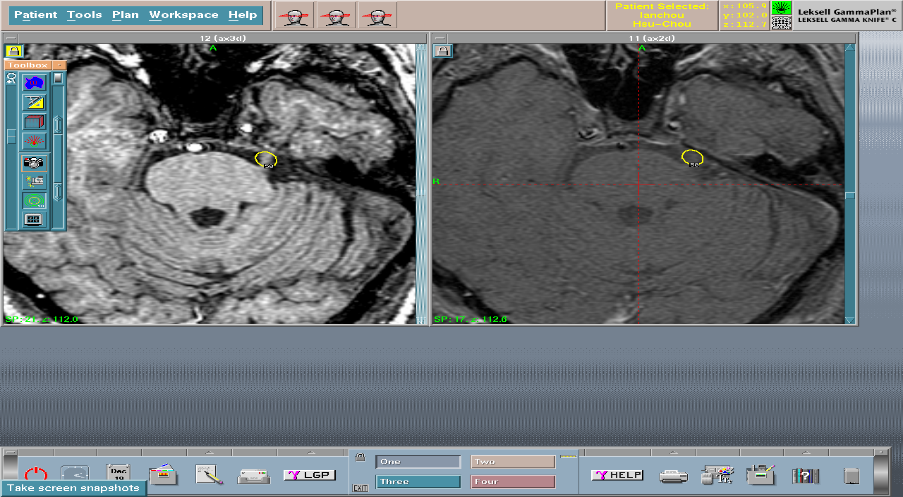

* 手術當天早上: 病患由病房送至加馬刀治療中心,先安置頭部立體定位頭架,再接受影像學檢查(磁振造影掃瞄MRI或電腦斷層掃瞄CT或血管攝影檢查Angiogram),檢查完畢後,再送回加馬刀治療中心。由治療小組利用影像學檢查結果,以精密的電腦程式 (Gamma Plan),設計完整的放射治療範圍及劑量。病患接受加馬刀放射手術治療。

動靜脈畸形

手術前

手術後